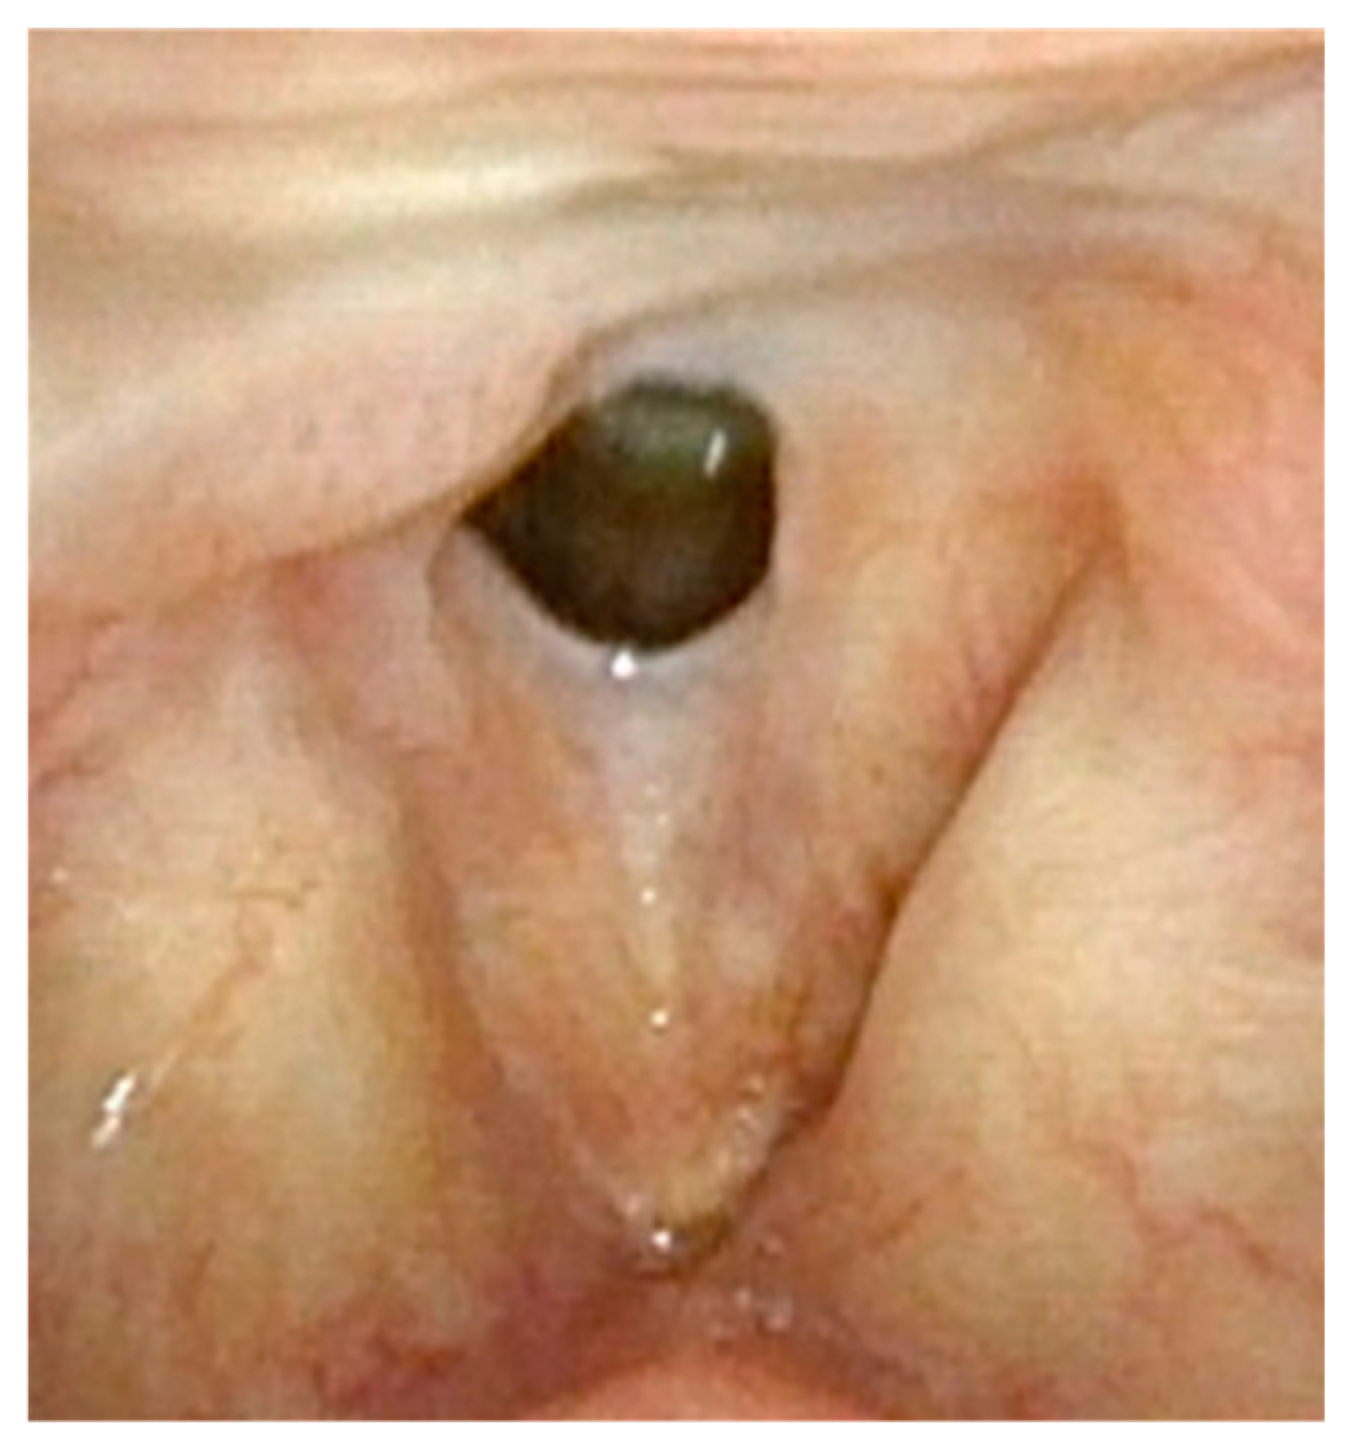

Figure 1 demonstrates a patient who had too aggressive anterior commissure laser treatment. A consequence of this was a very large anterior glottic web. Should this be encountered, the web may be lysed in the midline and steroid-injected (Figure 2). If the web is not the full thickness of the vocal folds, it should be cut with cold steel to help prevent the return of the web during healing. Once healed the web should be significantly improved (Figure 3). Consideration should be given to the dilation of the glottis following lysis.

Figure 1.

Large anterior glottic web with small amount of papilloma on right posterior commissure.